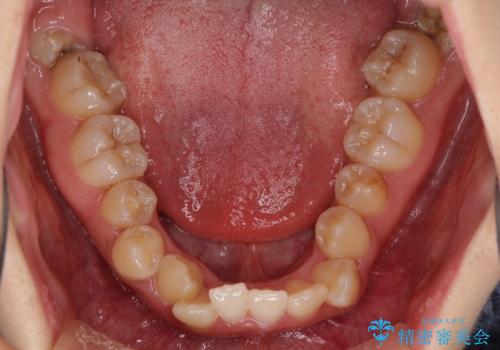

- 前歯の著しい叢生とクロスバイトを気にして来院された患者様です。

叢生が強いため、一見すると抜歯矯正と判断したくなりますが、下顎臼歯が舌側に倒れていることから、上顎骨を側方拡大し、非抜歯矯正の可能性を検討することとしました。

急速拡大装置による上顎骨の側方拡大が思った以上にうまくいき、非抜歯での矯正が可能となりました。

内側に倒れていた下顎の臼歯は起き上がり、清掃性も大幅に改善されました。